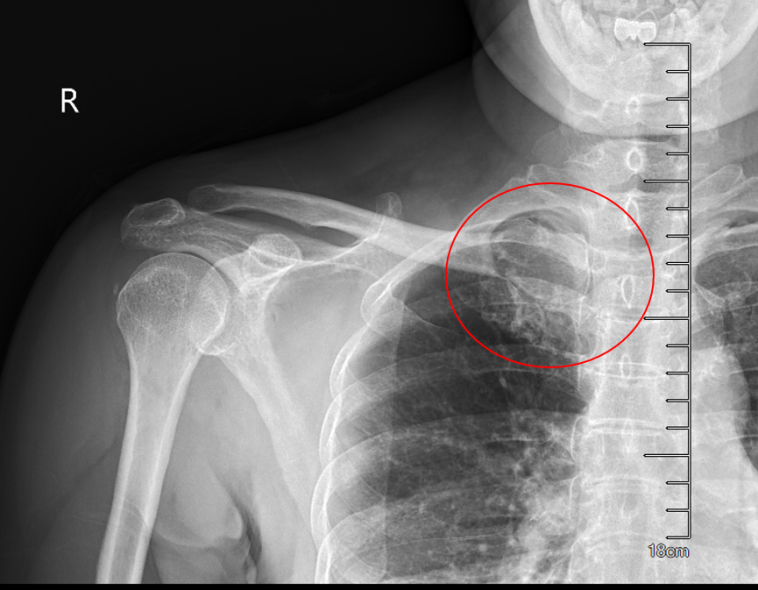

患者50岁女性,因体检发现右锁骨肿物10余天来诊。入院后X光片示右锁骨胸骨端膨大,密度减低,CT及MRI检查提示右侧锁骨局部骨性凸起伴周围肿块形成,考虑右锁骨胸骨端软骨肉瘤。

完善术前评估及准备后,王伟东副主任团队为患者实施了右锁骨胸骨端继发型软骨肉瘤扩大切除术+自体腓骨移植重建术。术中见肿物与颈总动脉、头臂静脉相邻紧密,王伟东副主任凭借扎实的手术技术,完整将肿瘤和临近大血管分离,完整切除肿瘤。目前患者伤口恢复良好,已逐步开始康复锻炼,肩关节活动无障碍。